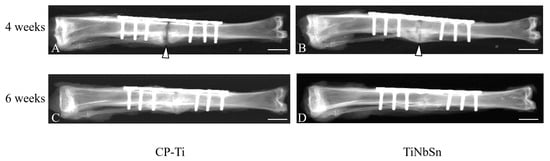

- Fujisawa, H.; Mori, Y.; Kogure, A.; Tanaka, H.; Kamimura, M.; Masahashi, N.; Hanada, S.; Itoi, E. Effects of intramedullary nails composed of a new beta-type Ti-Nb-Sn alloy with low Young’s modulus on fracture healing in mouse tibiae. J. Biomed. Mater. Res. B 2018, 106, 2841–2848. [Google Scholar] [CrossRef] [PubMed]

- Kogure, A.; Mori, Y.; Tanaka, H.; Kamimura, M.; Masahashi, N.; Hanada, S.; Itoi, E. Effects of elastic intramedullary nails composed of low Young’s modulus Ti-Nb-Sn alloy on healing of tibial osteotomies in rabbits. J. Biomed. Mater. Res. B Appl. Biomater. 2019, 107, 700–707. [Google Scholar] [CrossRef] [PubMed]

- Mori, Y.; Fujisawa, H.; Kamimura, M.; Kogure, A.; Tanaka, H.; Mori, N.; Masahashi, N.; Aizawa, T. Acceleration of Fracture Healing in Mouse Tibiae Using Intramedullary Nails Composed of β-Type TiNbSn Alloy with Low Young’s Modulus. Tohoku J. Exp. Med. 2021, 255, 135–142. [Google Scholar] [CrossRef] [PubMed]

- Koguchi, M.; Mori, Y.; Kamimura, M.; Ito, K.; Tanaka, H.; Kurishima, H.; Koyama, T.; Mori, N.; Masahashi, N.; Aizawa, T. Low Young’s Modulus TiNbSn Alloy Locking Plates Accelerate Osteosynthesis in Rabbit Tibiae. Tohoku J. Exp. Med. 2023, 261, 199–209. [Google Scholar] [CrossRef] [PubMed]